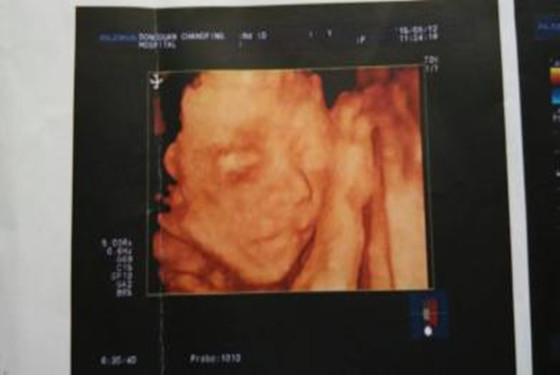

四维超声同其它超声检查相比,可以实时观察人体内部器官的动态运动,也能准确地分辨出胎儿的性别。虽然四维彩超能够看清胎儿的性别,但在检查过程中,为了避免透露胎儿的性别,医生会主动的回避胎儿的性别特征以及下半身,同时,在后期制作光盘时,也会将可能泄露胎儿性别的部分进行处理。

3、通过四维彩超图看清胎儿性别,在孕前期的时候做四维彩超,能够照到全部,孕妈仔细观察你会发现哦!